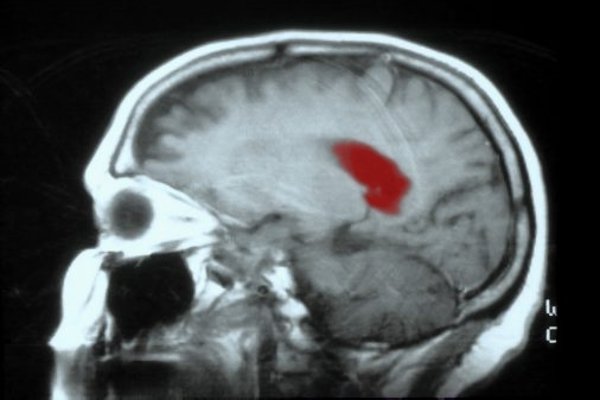

Американские ученые нашли эффективное средство, препятствующее росту глиобластомы. Об этом сообщил портал MedicalNewsToday.

Группа исследователей занимается изучением глиобластомы уже несколько лет. За это время стало известно, что клетки опухоли содержат высокую концентрацию фермента CDK5, заблокировав который можно остановить рост глиобластомы.

По словам исследователей, разработанный метод можно использовать для лечения нейронального и классического подтипов глиобластомы. При мезенхимальной форме болезни уровень CDK5 практически не повышается, что делает ингибитор CDK5 малорезультативным.

Препарат получил рабочее название CP681301. К сожалению, не все подтипы глиобластомы оказались восприимчивы к новому лечению.

Глиобластома относится к наиболее агрессивным и неподдающимся лечению формам опухоли мозга. Продолжительность жизни больного после постановки диагноза составляет менее года. Уникальность заболевания проявляется в особой субпопуляции раковых клеток.